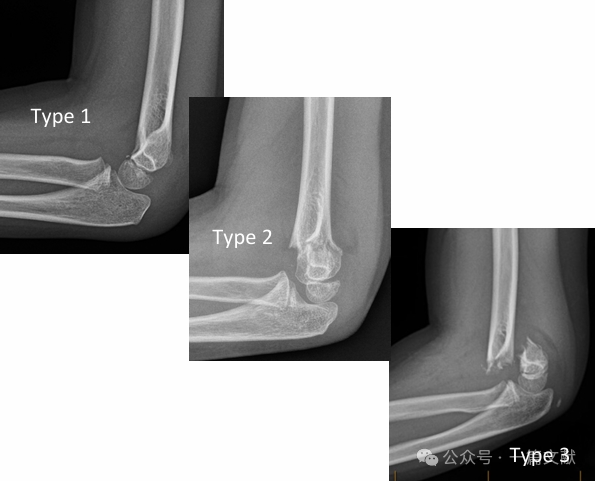

* Classic Gartland Classification:

* Type 1: Nondisplaced.

* Type 2: Displaced fracture, but with an intact posterior hinge.

* Type 3: Displaced fracture with disruption of the posterior hinge.

* Type 3: Complete posterior displacement with disruption of the posterior hinge mechanism; periosteal sleeve is intact.

* Type 4: Unstable in both extension and flexion; periosteal sleeve is disrupted.